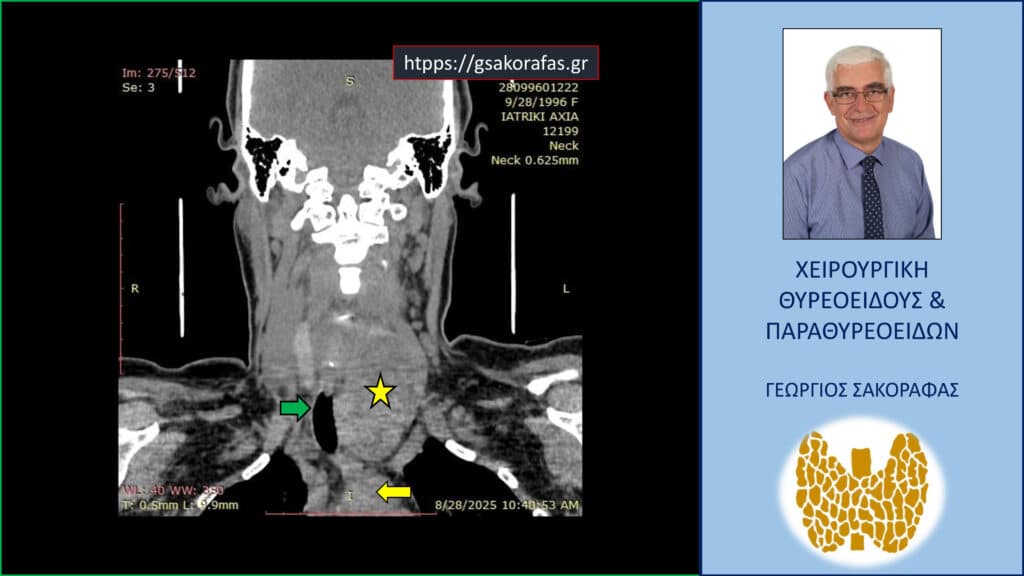

- Γιατί είμαστε σε θέση να εκτελέσουμε με ασφάλεια και αποτελεσματικότητα κάθε είδους χειρουργική επέμβαση θυρεοειδούς – παραθυρεοειδών, ακόμη και σε επιπλεγμένα (δύσκολα) περιστατικά, όπως εκτεταμένοι λεμφαδενικοί καθαρισμοί σε καρκίνο θυρεοειδούς, επεμβάσεις σε λίαν ευμεγέθεις καταδυόμενες στο μεσοθωράκιο βρογχοκήλες, υποτροπές παθήσεων θυρεοειδούς (συμπεριλαμβανομένου του καρκίνου θυρεοειδούς), υποτροπές υπερπαραθυρεοειδισμού, αδενώματα παραθυρεοειδών σε έκτοπη θέση ή λόγω υπεράριθμων παραθυρεοειδών, διάχυτη υπερπλασία παραθυρεοειδών, κλπ.